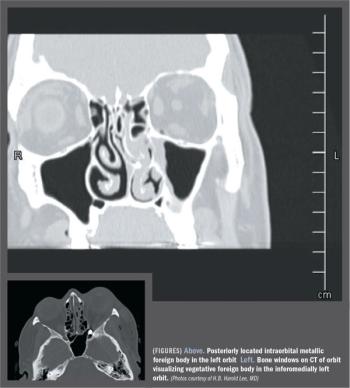

Removal of object may depend on potential risk, impact on patient’s vision